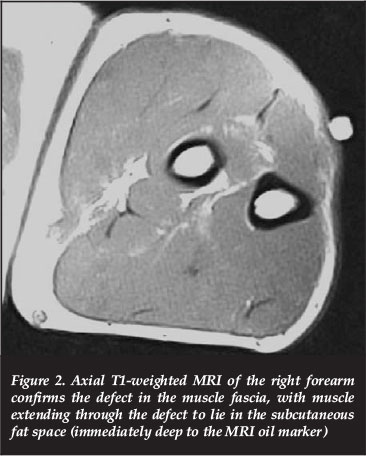

The ultrasonographic findings were confirmed by MRI, using fast spin echo (FSE) images in the axial, coronal and sagittal planes before and after muscle contraction. MRI demonstrated the size of the muscle herniation and the extent of the fascial defect while the forearm was contracted (Figure 2). Again no features of chronic exertional compartment syndrome were present. The patient was advised of the diagnosis and referred to the orthopaedic department.

MRI is not operator-dependent, and its findings are reproducible. MRI may help in the evaluation of the amount of soft tissue oedema and the identification of the specific muscles and structures involved. MRI of a muscle hernia is a visualised local defect, with measurable size and extent of the fascial defect.2 MRI of chronic exertional compartment syndrome may be noted as either a focal area of signal change or as an area of diffuse signal change within an osteofascial plane.